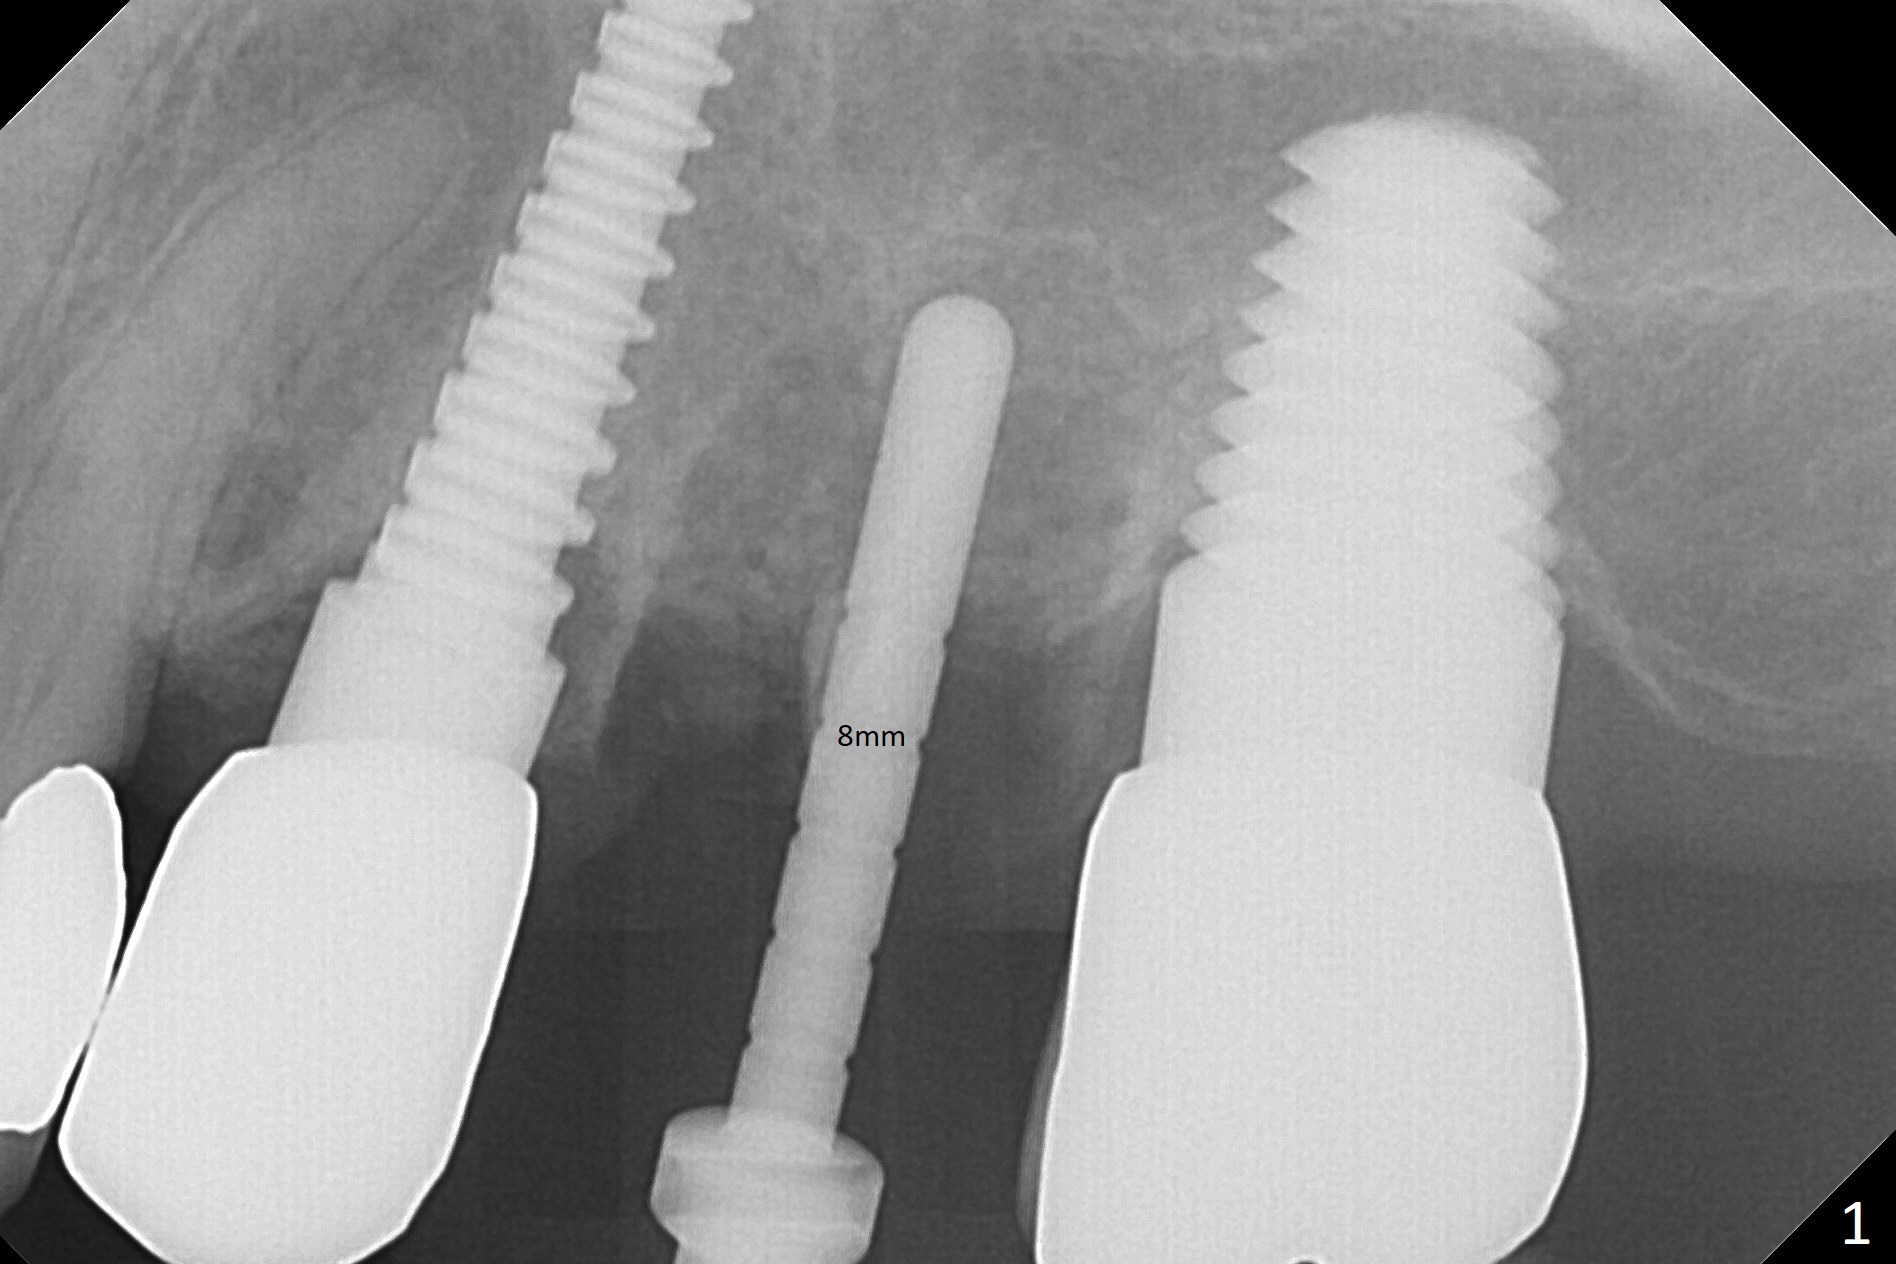

Initial osteotomy in the septum of the tooth #14 is 9 mm, approximately 2 mm from the sinus floor (Fig.1). Subsequent osteotomy depth is 11 mm, followed by insertion of a 4.5x11 mm dummy implant (Fig.2). After use of Magic Drill (MD) 4.8 mm for 9 mm, a 5x11 mm IBS implant is placed with sinus lift without additional bone graft (Fig.3 *). In contrast, autogenous bone (from MD) and Vanilla Graft are meticulously placed in the remaining socket (+) before and after placement of a 6.5x5.7(2) mm abutment. An immediate provisional is fabricated to close the sockets. There is buccal tenderness 1-3 months postop. There is distopalatal implant thread exposure. A healing abutment (5.5x2 mm) is placed. CT confirms thin buccal plate (Fig.4,5). It appears that the implant should have been as palatal as possible. The tenderness remains for the next 2 weeks. When the healing abutment is removed, the implant seems to have been placed shallow, ~ 1 mm subgingival (Fig.6). With local anesthesia, the implant is reversed to clean the coronal threads with Titanium brush and copious irrigation (Fig.7). The implant is then placed ~4 mm subgingival (Fig.8) and slightly subcrestal (Fig.9,10). It appears that the postop bone loss (Fig.9 *, as compared Fig.1,2) makes the implant look to be placed too shallow. When the implant is being placed deeper, the buccal plate feels intact. The early periimplantitis is apparently due to postop bone loss more than buccal placement, although certain degree of buccal bone resorption must occur. A 6x4 mm healing abutment is placed. Left facial swelling develops 2 days post implant elevation (Fig.11,12, as compared to preop (Fig.13)). The left maxillary sinus cloud (Fig.12) appears to be a false positive finding, since the same feature exists prior to implant elevation (Fig.13). Both sinuses look clear prior to implant elevation (Fig.14). Amoxicillin switches to Augmentin and Flagyl, since the patient is reluctant to have the implant removed. Finally the sinus infection is under control. The patient feels left facial swelling 9 months postop (5 months post elevation) and reports left nasal discharge ~ 1 month earlier. There is mild buccal plate tenderness. The implant seems to be buccally placed (Fig.15,16), although there is no significant change radiographically (Fig.17). The implant is removed with bone graft (Fig.18 *). To avoid complication and failure, an immediate implant at the upper 1st molar should be short and placed deep.